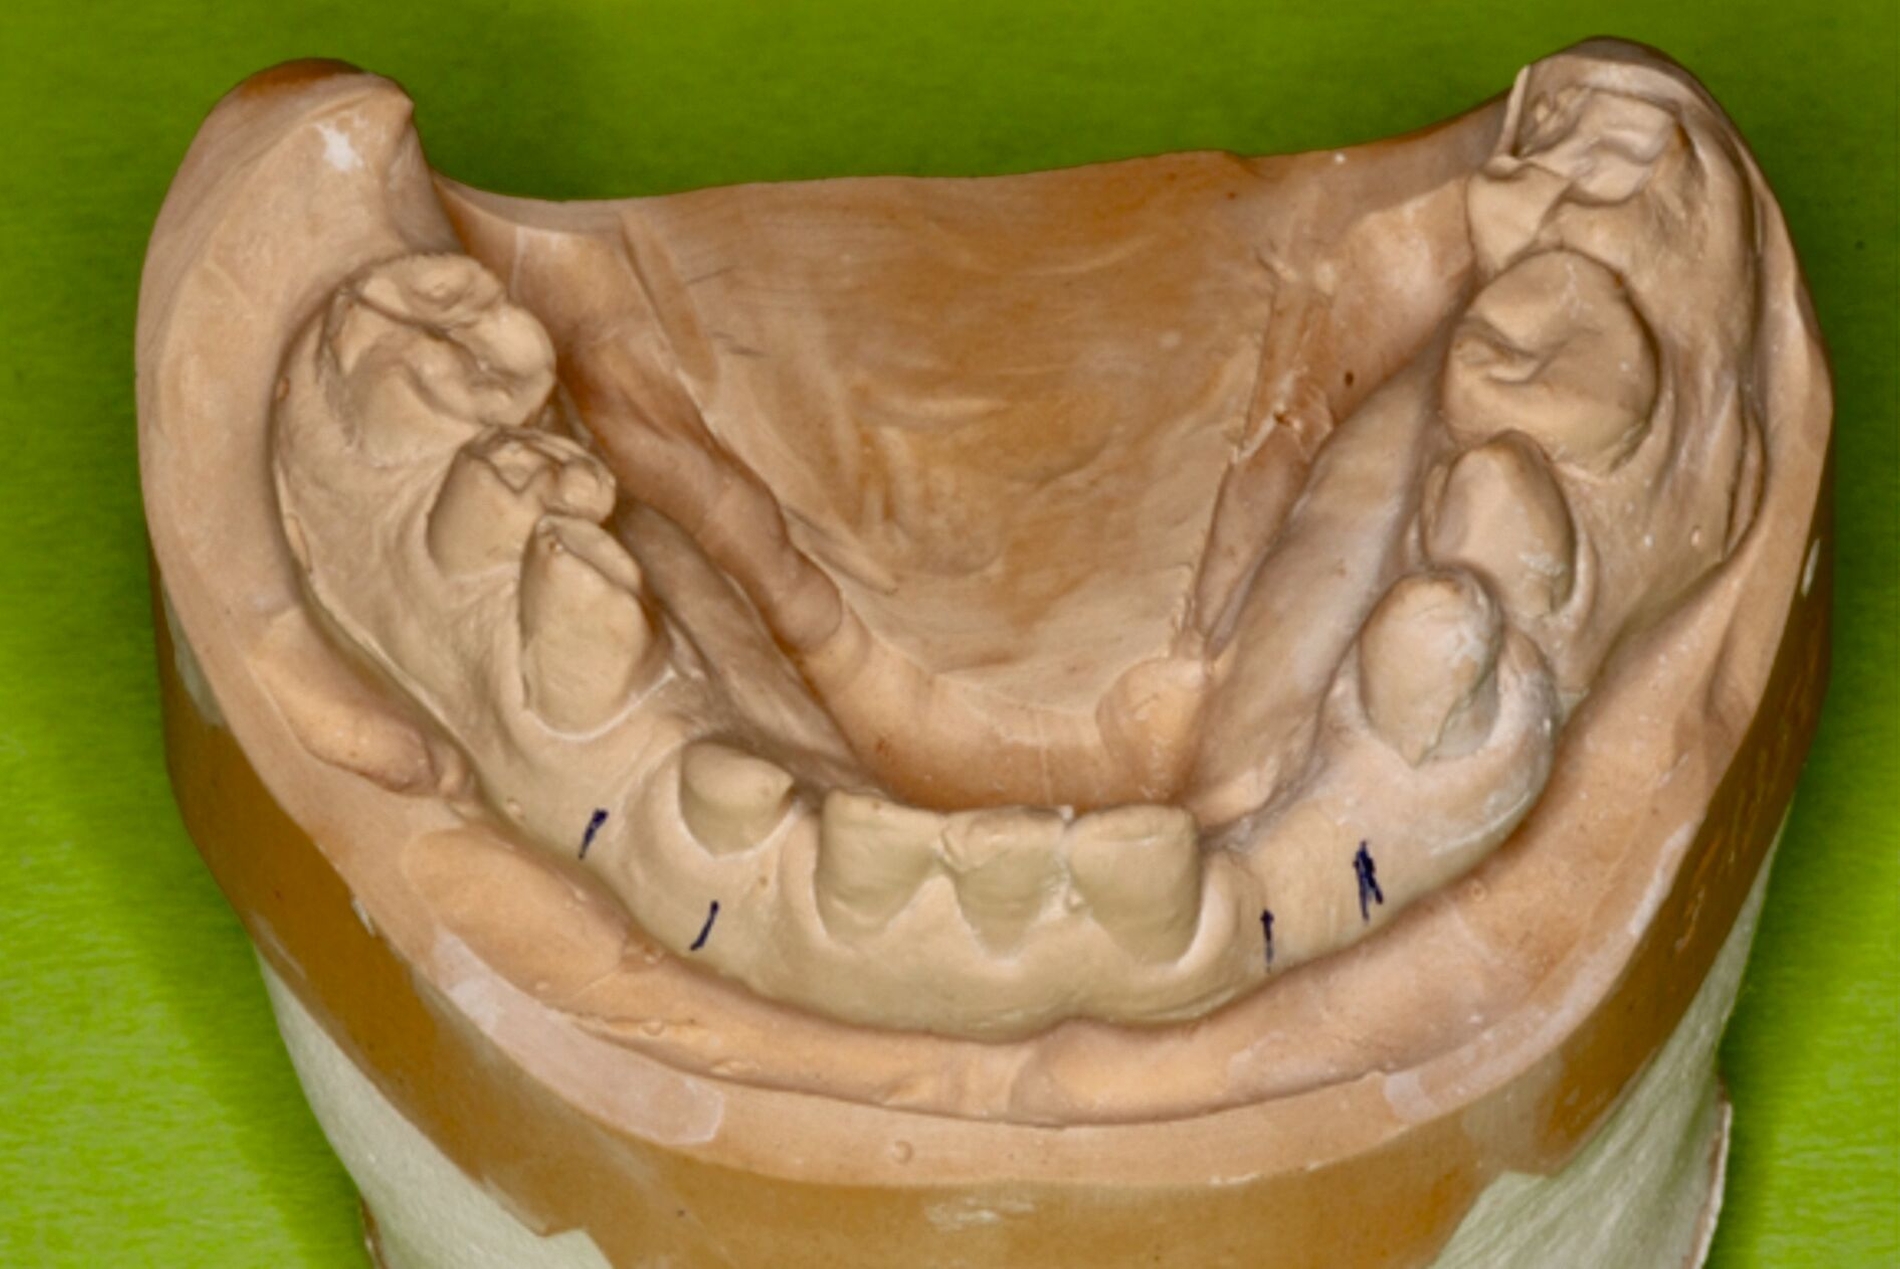

Zu Beginn der Behandlungsplanung wurden ein digitales OPG sowie Planungsmodelle erstellt (Abbildung 2). Interdisziplinär wurden mit dem Prothetiker, Chirurgen und Zahntechniker anhand der vorliegenden Modellanalysen und der klinischen Situation des Patienten verschiedene Therapieoptionen entwickelt und gemeinsam bewertet.